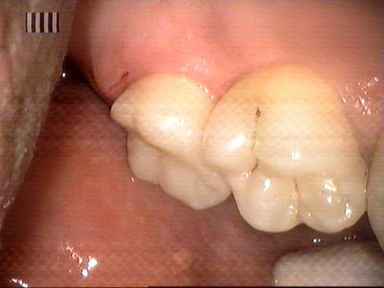

Leczenie próchnicy wtórnej ostatniego górnego trzonowca. Ze względu na trudny dostęp ząb odbudowano laboratoryjnie wykonanym wkładem kompozytowym.